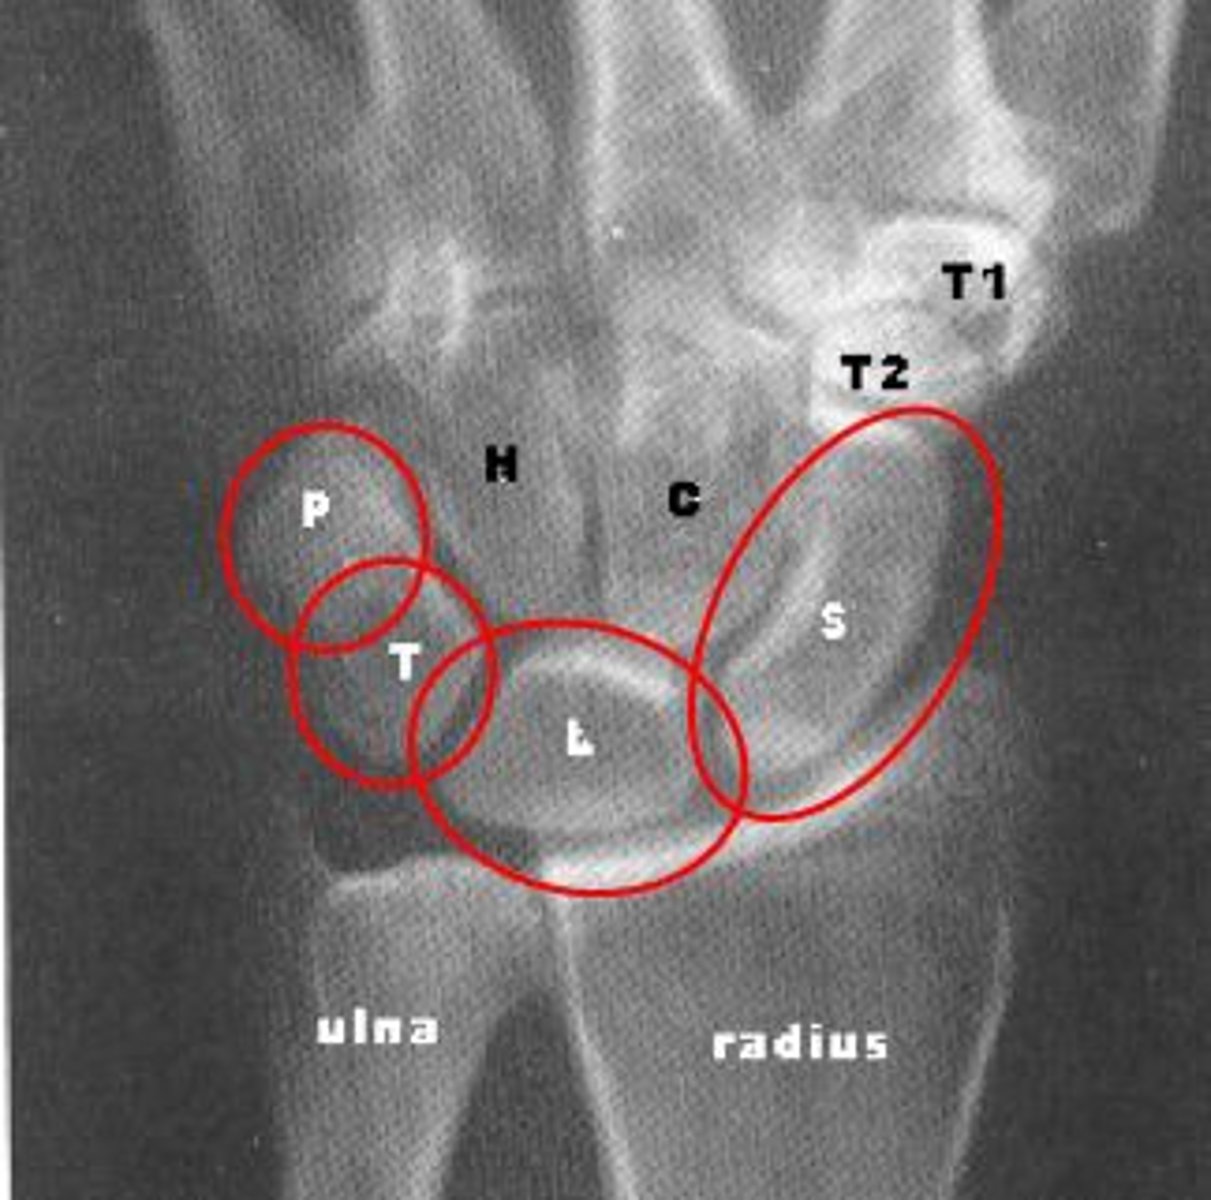

proximal row of carpals

No direct tendon attachments

⢠Acts as an intercalated segment

⢠Highly mobile ā prone to instability

lateral to medial: scaphoid, lunate, triquetrum, pisiform

distal row of carpals

Strong ligamentous connections

⢠Moves as a rigid unit

⢠Provides stability for grip and load transfer

Includes: Trapezium, Trapezoid, Capitate, Hamate

Scaphoid

carpal bone, closest to the radius, the "some" in the acronym Some Lovers Try Positions That They Can't Handle

Lunate

carpal bone that's shaped like a crescent moon, "lovers" in the acronym Some Lovers Try Positions That They Can't Handle

Triquetrum

the "try" in the acronym Some Lovers Try Positions That They Can't Handle, Pisiform is often attached to this carpal bone

Pisiform

Pea-shaped bone often shown attached to the triquetrum

Trapezium

carpal bone that is closest to the the thumb, the "that" in the acronym Some Lovers Try Positions That They Can't Handle

Trapezoid

thumb side of the hand, "they" in the acronym Some Lovers Try Positions That They Can't Handle

Capitate

carpal bone, the "capital" in the center of the hand, "can't" in the acronym Some Lovers Try Positions That They Can't Handle

Hamate

carpal bone towards the pinky side, has a projection that sort of looks like a ham bone